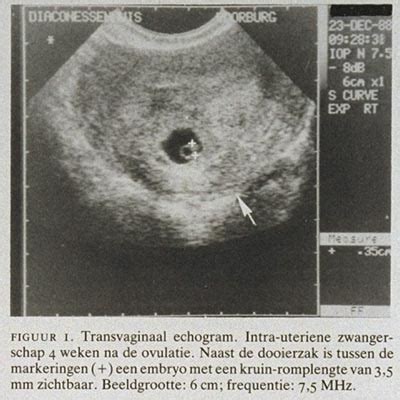

Zichtbaarheid op echo's en de vruchtzak

Rond 4 tot 5 weken zwangerschap kan de vruchtzak al zichtbaar zijn op een echo als een klein, rond blaasje. Naarmate de zwangerschap vordert, groeit de vruchtzak en wordt het embryo duidelijker zichtbaar. Rond week 6 kan de arts via echografie de hartslag van het embryo vaststellen, wat wijst op een zekere ontwikkeling van het zenuwstelsel.

De vruchtzak, bestaande uit het amnion en chorion, speelt een cruciale rol in de bescherming van de baby en het produceren van vruchtwater. Bij meerlingen kan de structuur van de vruchtzakken variëren.